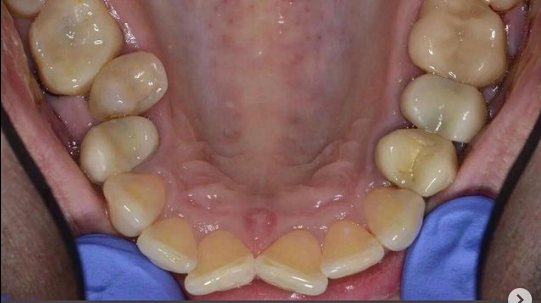

Врач Заводова (Рыбась) Анна Викторовна принимает в стоматологическом комплексе ПРЕЗИДЕНТ НА ЛЮБЛИНСКОЙ в Москве. Имеет рабочий стаж 21 год. Специализируется на ортодонтии, по которой клиника оказывает 3 услуги. Имеет 4 работы до/после в портфолио. Квалификация специалиста подтверждена 15 лицензиями, сертификатами и наградами. Для уточнения дополнительной информации о специалисте или записи на прием можно позвонить по телефону

Установка брекетов

Установка брекетов в Москве